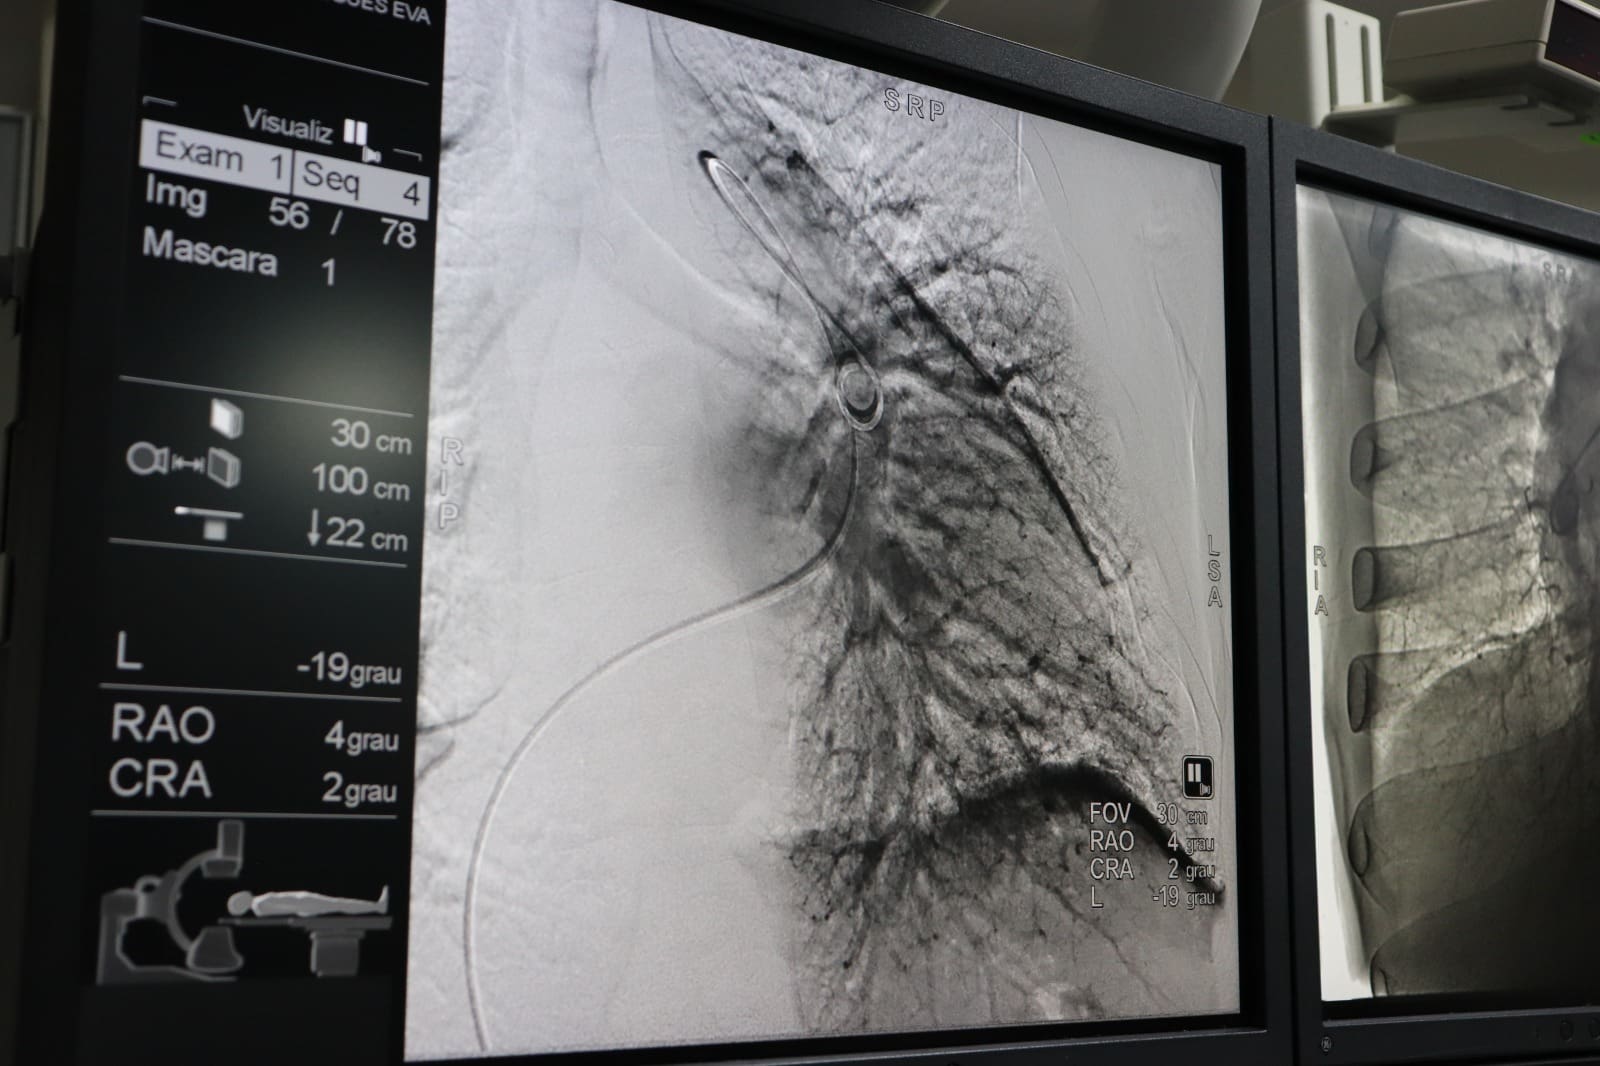

Agora realizada no HGG, angioplastia pulmonar é feita por cateterismo cardíaco, em pacientes com hipertensão pulmonar tromboembólica (Fotos: Idtech)

O Hospital Estadual Dr. Alberto Rassi (HGG) é o único hospital público em Goiás a oferecer angioplastia pulmonar por balão. O procedimento é feito por meio de cateterismo cardíaco, em pacientes com hipertensão pulmonar tromboembólica causada por coágulos de sangue, que provocam a obstrução de parte dos vasos sanguíneos, dificultando a circulação do sangue nos pulmões e causando falta de ar.